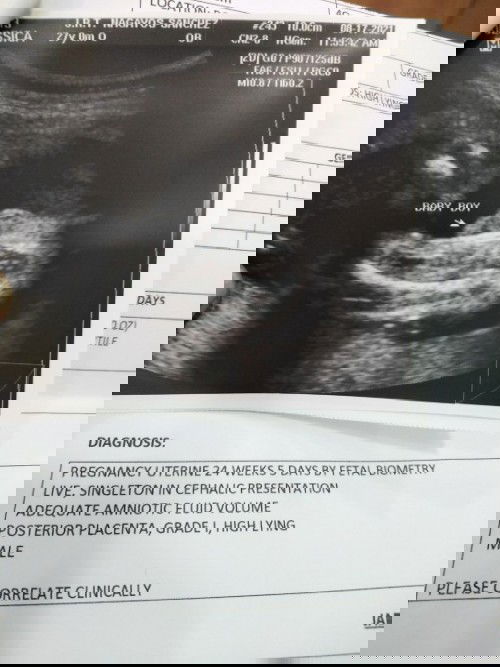

Ask kopo sana kung sure ba na Boy Gender ni baby ko base Utz ko. THANK YOU β€οΈπŸ™

Hehe opo baby boy. Pag girl, may hati sa gitna at hndi ganyan katambok